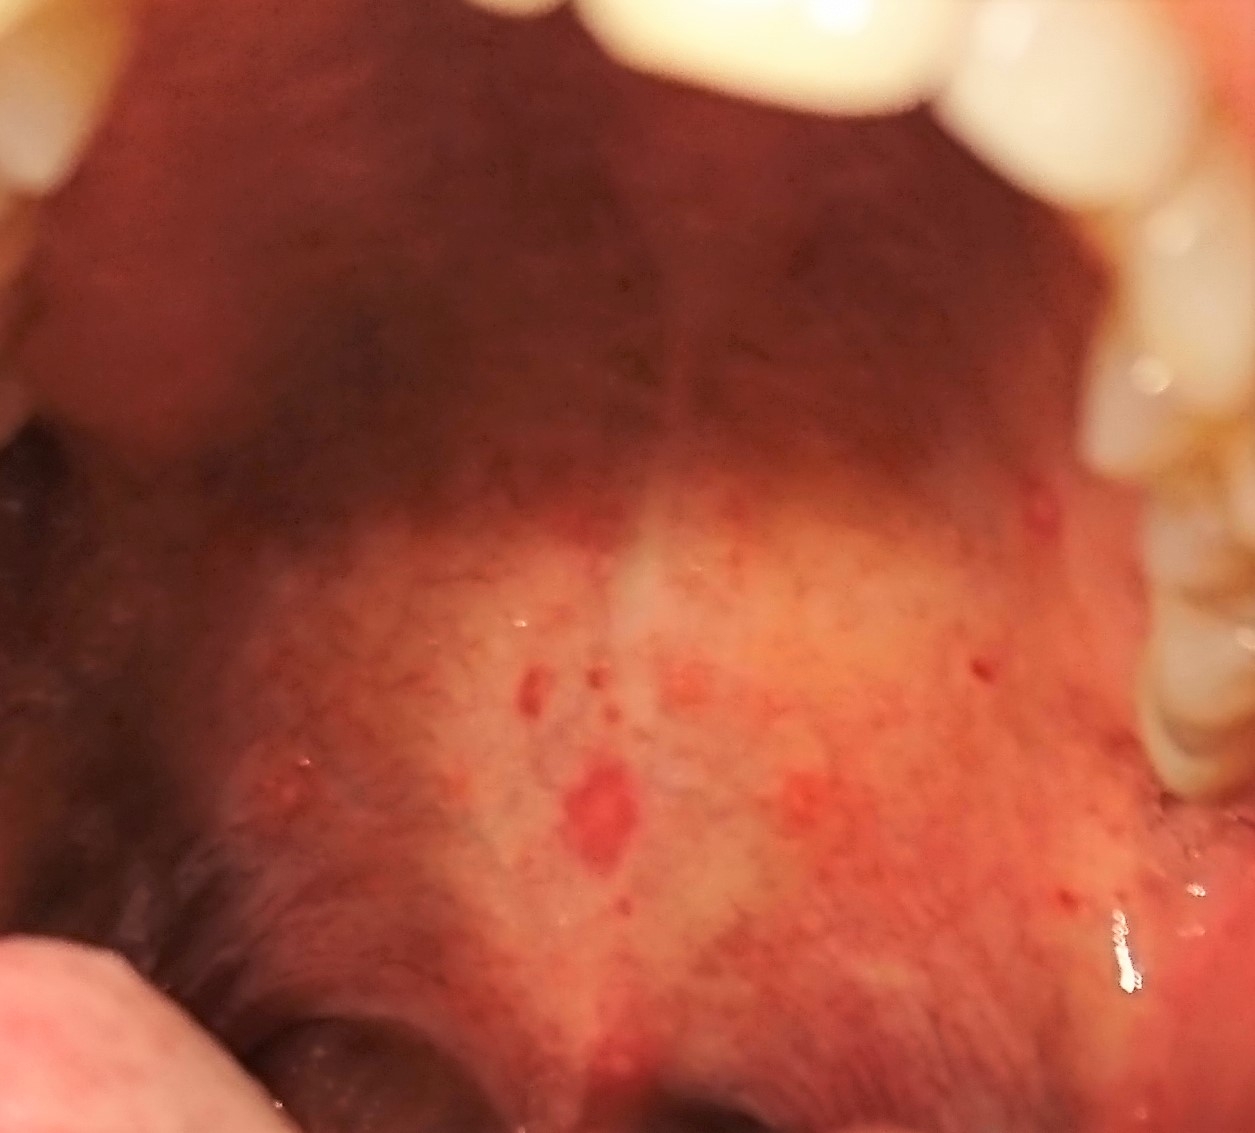

ダブルでできてる口内炎

ダブルでできてる口内炎 レーザー照射後